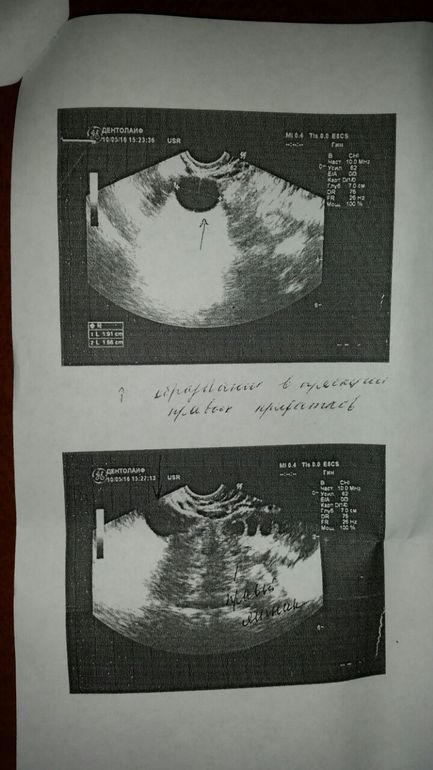

Девочки, сегодня была у своего Г. Принесла ей результаты вчерашнего узи. Овуляцией на нем не пахнет. Плюс за пределами правого яичника просматривается образование. Узист сказала, что это похоже на фрагмент воспаленной трубы, либо параовариальная киста. Когда я показала это узи своему врачу, она долго его изучала, потом долго изучала мою карточку и сказала, что ей надо все хорошо еще раз просмотреть и обдумать и выписала мне направление на этот анализ. Я к ней пришла уже в неприемное время после своей работы, нормально расспросить ее не удалось. Мне кажется, она что-то недоговаривает. Пришла домой, разревелась. Пугает слово онкомаркеры... фото узи подкат